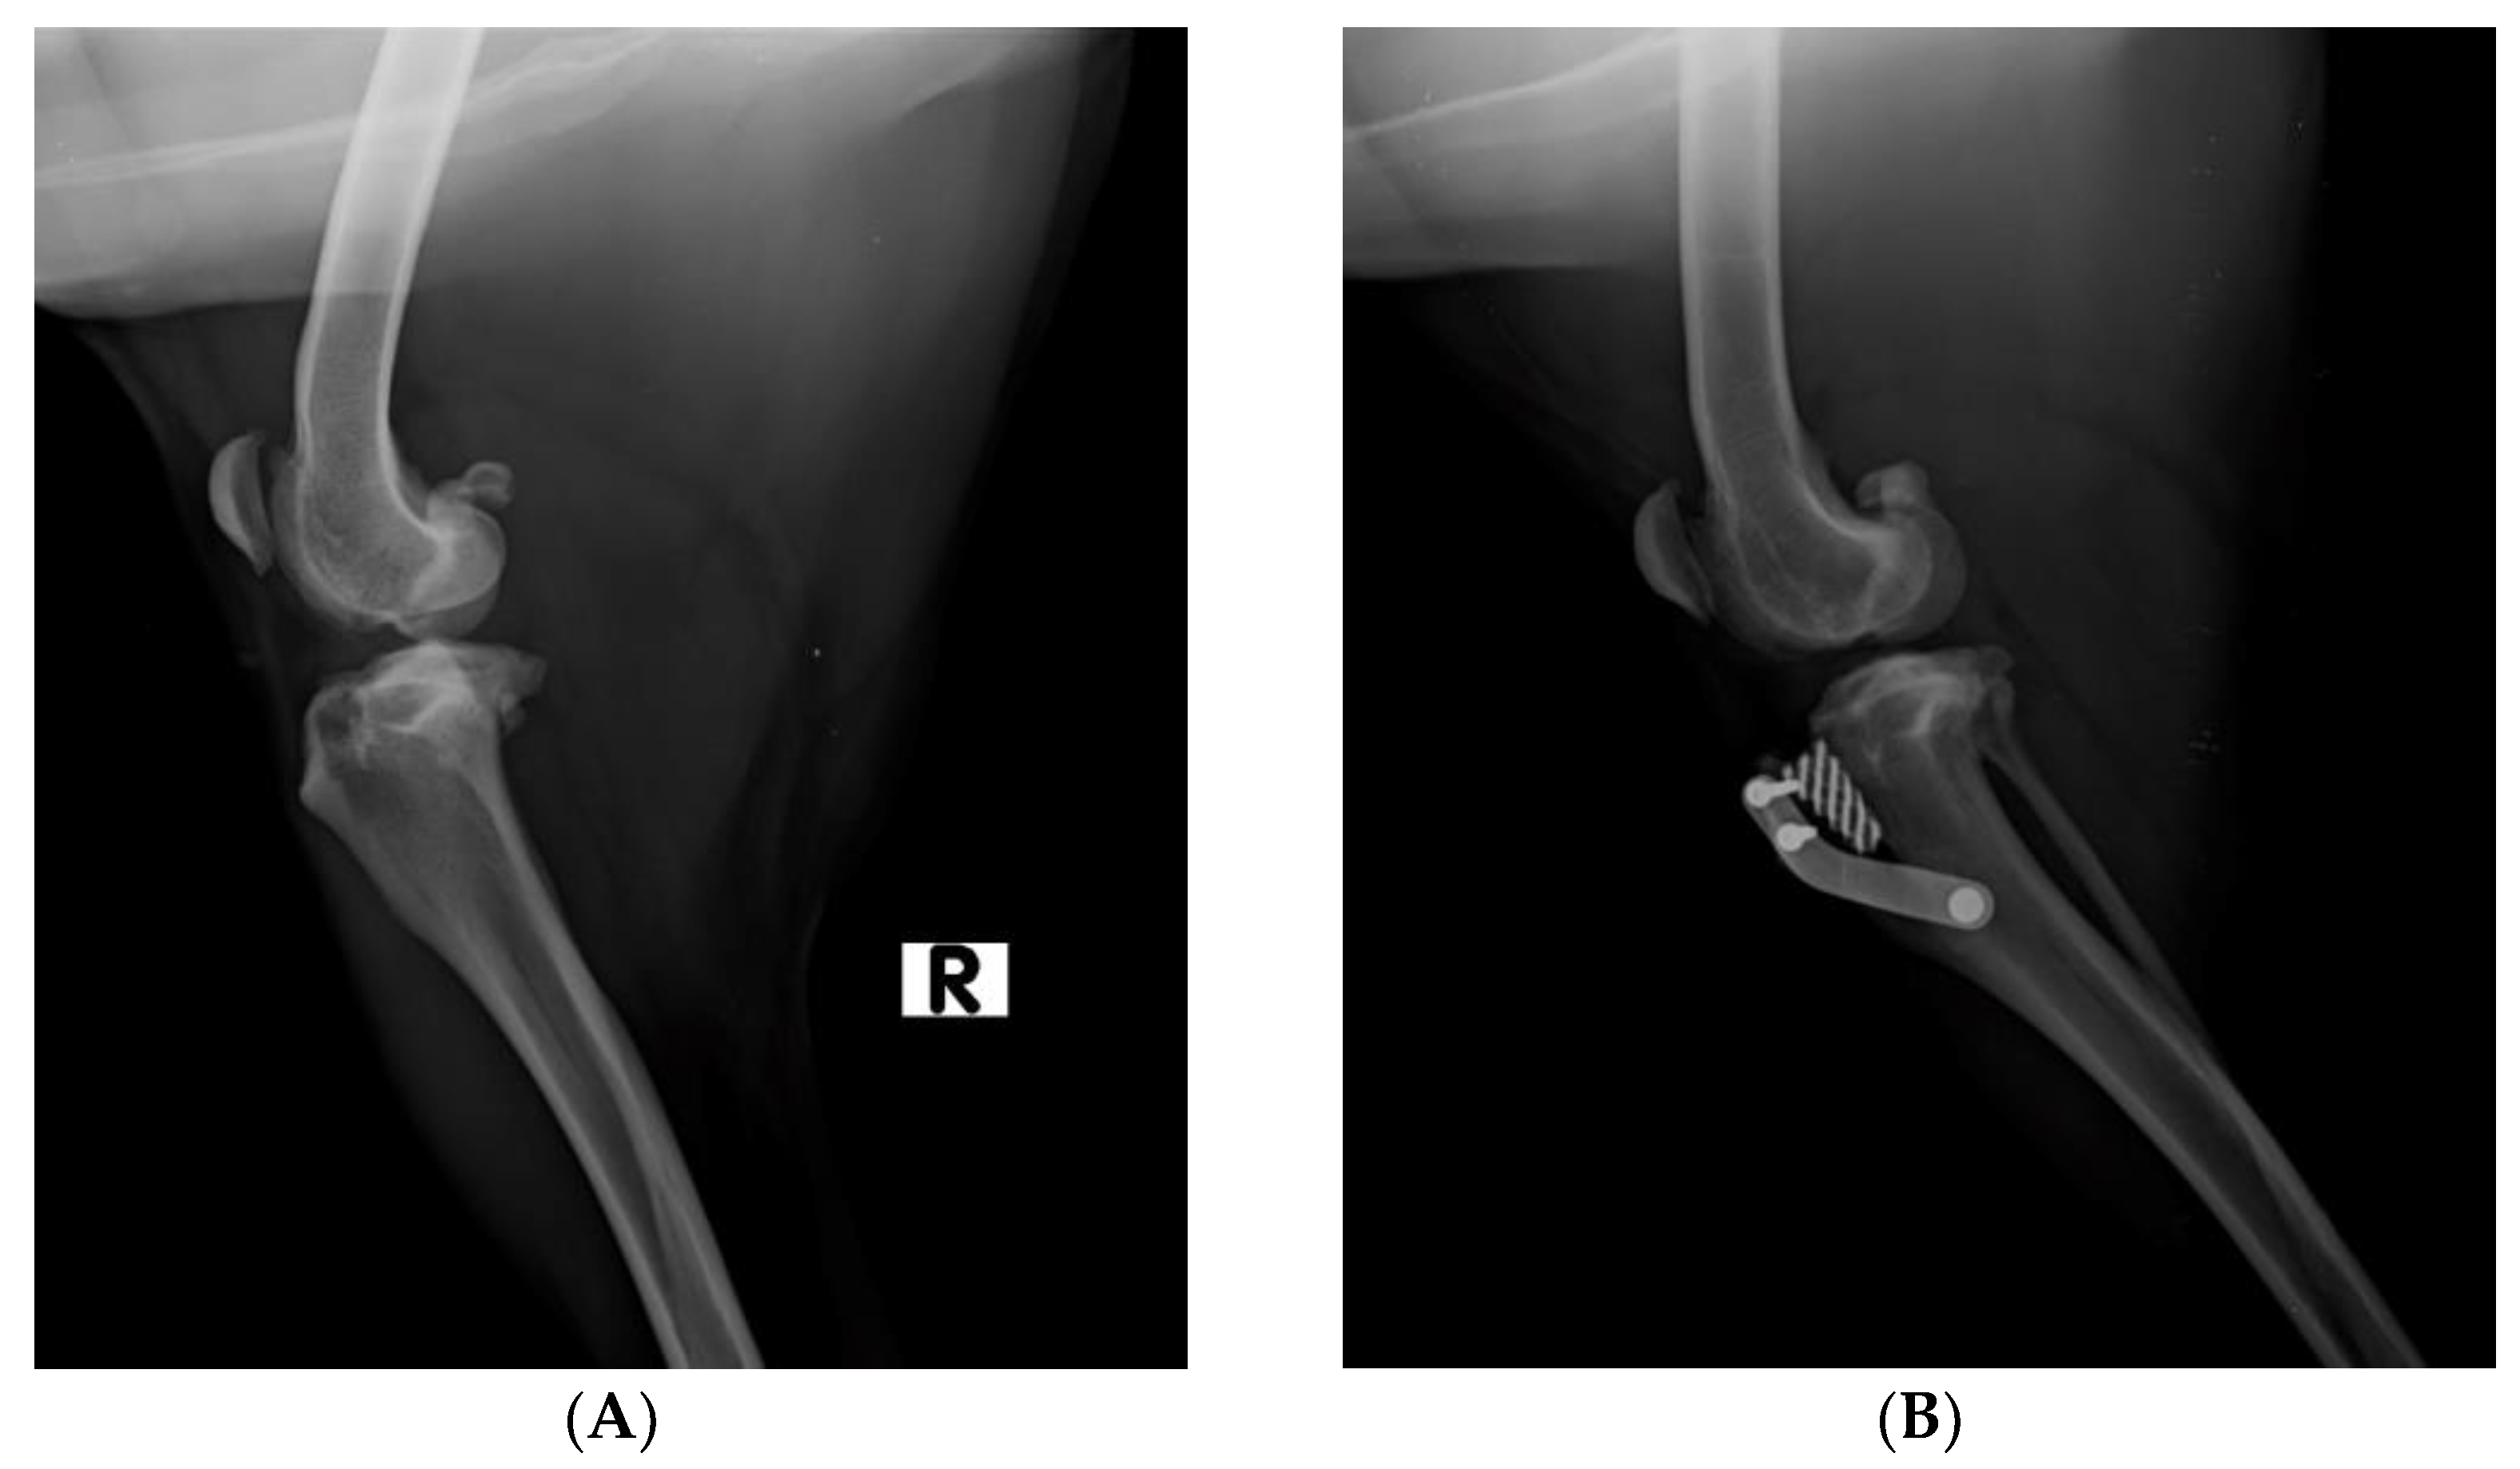

2.2. Surgical Procedure